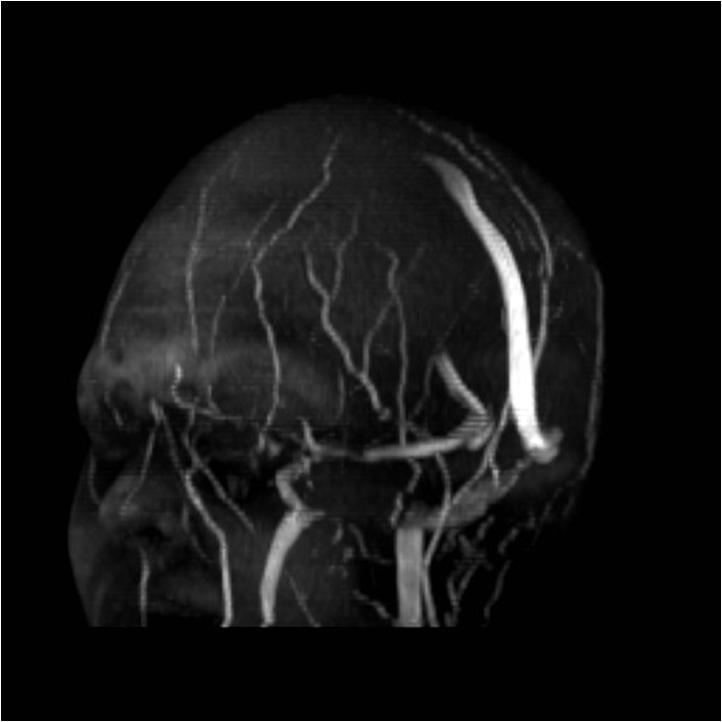

MRI findings of IIH patients and control group Download Scientific Diagram Iih Imaging Findings — secondly, imaging can show findings that support the diagnosis of iih such as enlargement of the perioptic csf spaces, tortuosity of the optic nerves,. we evaluated five imaging findings as described in 21 patients with proven iih and 60 patients with secondary intracranial. — the clinical picture of iih is dominated by headache and ophthalmic features. Iih Imaging Findings.

MRI findings of IIH patients and control group Download Scientific Diagram Iih Imaging Findings — secondly, imaging can show findings that support the diagnosis of iih such as enlargement of the perioptic csf spaces, tortuosity of the optic nerves,. — clinical picture. — iih is diagnosed on the basis of high intracranial pressure, measured via lumbar puncture, and the absence of mass. — the clinical picture of iih is dominated. Iih Imaging Findings.

MRI findings of IIH patients and control group Download Scientific Diagram Iih Imaging Findings we evaluated five imaging findings as described in 21 patients with proven iih and 60 patients with secondary intracranial. — secondly, imaging can show findings that support the diagnosis of iih such as enlargement of the perioptic csf spaces, tortuosity of the optic nerves,. — the clinical picture of iih is dominated by headache and ophthalmic features. Iih Imaging Findings.